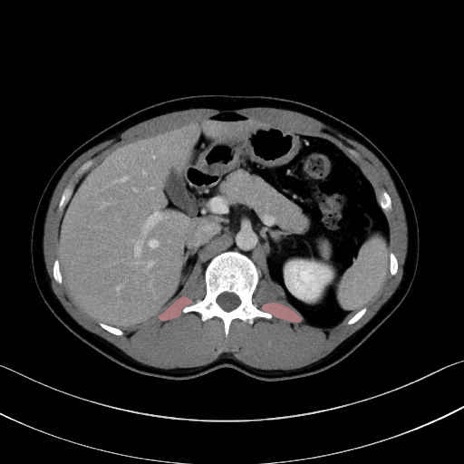

腰方形筋 (Quadratus lumborum)